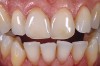

1. Substrate

The first consideration is evaluating the substrate to which the material will be attached (Figure 1). Is it enamel? How much of the bonded surface will be enamel? How much enamel is on the tooth? Is it dentin? How much of the bonded surface will be dentin? What type of dentin will the restoration be bonded to (ie, tertiary or sclerotic dentin exhibits very poor bond strength, and bonding to this type of dentin should be avoided when possible)? Is it a restorative material (eg, composite, alloy)? These questions should be addressed for each tooth to be restored because this will be one major parameter for material selection.

Figure 1  Image of the prepared tooth. Significant dentin is exposed. The proposed length flexure and tensile stress risk is at least medium and the restoration thickness would be at least 0.9 mm. This was noted in the chart.

Figure 1